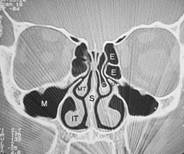

Da man sich als Laie schlecht vorstellen kann wo genau diese Nasenmuscheln in der Nase sitzen hier zusätzlich zu dem oberen Bild ein frontaler Querschnitt durch das Mittelgesicht:

Abb. 1   Abb. 2

Abb. 1: Hier relativ normale Verhältnisse. Die Nasenmuscheln lassen noch genügend Luft (schwarz) durch die Nasenhöhle strömen obwohl die Scheidewand leicht verkrümmt ist

Erklärung: Schwarz: Luft, Graustufen: Weichteile, Weiß: Knochen, IT: untere Nasenmuschel, M: Kieferhöhle, S: Nasenscheidewand